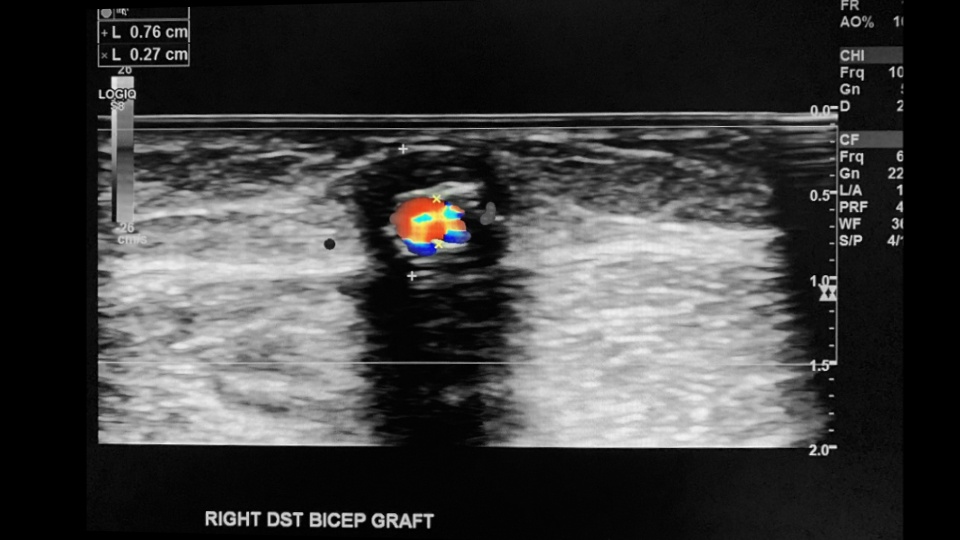

An AV-graft is also created surgically by using a small hollow, synthetic tube that connects the artery to the vein. The material used is usually a Polytetrafluoroethylene (PTFE) aka Gore-Tex tube. Grafts are used as opposed to fistulas when the patient’s native vasculature is not suitable for fistula creation. The graft can be straight or looped.

- Scan the proximal, mid and distal sections of the graft/fistula (outflow).

- Pay close attention to previous puncture sites along the graft/fistula.

- Assess for pseudoaneurysm, stenosis, thrombosis, occlusion and collections.